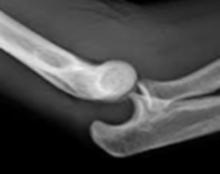

06. LUXACIÓN DEL CODO

Generalidades Clínica

La luxación posterior es la más frecuente, sobre todo, en niños y la segunda luxación más frecuente en el adultos después de la luxación de hombro.

Dolor, impotencia, deformidad en forma de hachazo tricipital. También genera rigidez e inestabilidad. Deformación del triángulo de Nelaton. Puede lesionar el nervio mediano

Las luxaciones anteriores de codo están asociadas a fracturas de olécranon (lesión de Hume). El manejo es quirúrgico, siendo el cerclaje con alambre el procedimiento de elección por la alta probabilidad de desplazamiento del fragmento roto.

Tratamiento

El manejo es ortopédico mediante reducción, inmovilización en 90° y rehabilitación temprana. En caso se confirme una fractura de olécranon, se debe tratar de forma quirúrgica e incluye cerclaje más alambre en el olécranon. (ENAM 2019-A)